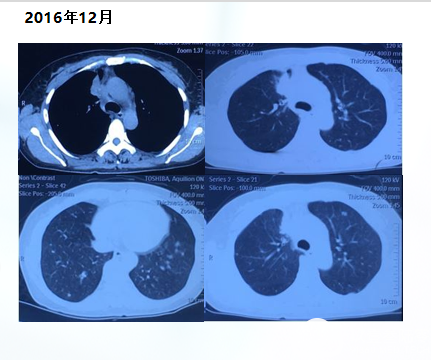

2016年12月14日首次入我院

主诉:面部浮肿,胸闷2月,确诊肺癌7天,一周期化疗后

现病史:郑大一附院CT发现右上肺占位、多发转移,肺穿刺诊断为右肺腺癌,IV期,脑转移,肺转移,纵隔转移,多发骨转移,胸11、腰5、骶1椎体、髂骨转移。培美曲塞化疗一周期,并口服易瑞沙,因口腔溃疡,恶心呕吐来我院。

基因检测结果:EGFR基因19号外显子突变

诊断: 右上肺腺癌 cT2N3M1 IV期 EGFR 19突变

脑转移,双肺转移,纵隔淋巴结转移,多发骨转移,胸11、腰5、骶1椎体、髂骨转移

治疗方案:

2016年12月05日开始

吉非替尼250mg,qd,po

唑来膦酸4mg q28天